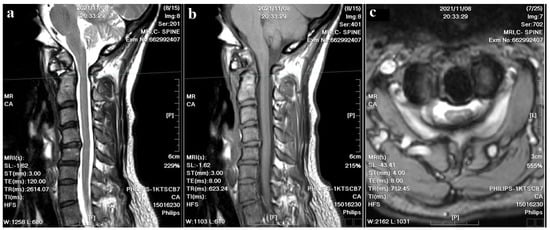

A 37-year-old female with no prior medical history or spinal surgeries presented to our neurosurgery outpatient department five months after a motorcycle traffic accident. Initially diagnosed with a C2 fracture at a local emergency department, she received only conservative treatment and wore a neck collar. Subsequent to the accident, she experienced persistent neck pain radiating to both shoulders and upper back, right-hand numbness with associated weakness, headaches, neck stiffness, and an unsteady gait. An initial cervical spine X-ray revealed the asymmetric widening of the distance between the right C1 arch and the dens with suspected atlantoaxial subluxation (Figure 1). Computed tomography revealed non-fused bony elements (Figure 2). Further cervical spine magnetic resonance imaging (MRI) (Figure 3) highlighted os odontoideum with C1-C2 subluxation and slight spinal cord atrophy at the C1-C2 level due to instability. There was also evidence of ventral compression at the C1-C2 level from chronic inflammatory pannus and granulation tissue.

Figure 3. Cervical spine MRI images. (a) The T2–weighted sagittal image revealed C1-C2 subluxation and slight spinal cord atrophy; cord edema and inflammatory pannus were also noted at the C1-C2 level. (b) The T1–weighted sagittal image showed evident ventral compression at the C1-C2 level. (c) The T2-weighted axial image showed a compressed spinal canal at the C1-C2 level.